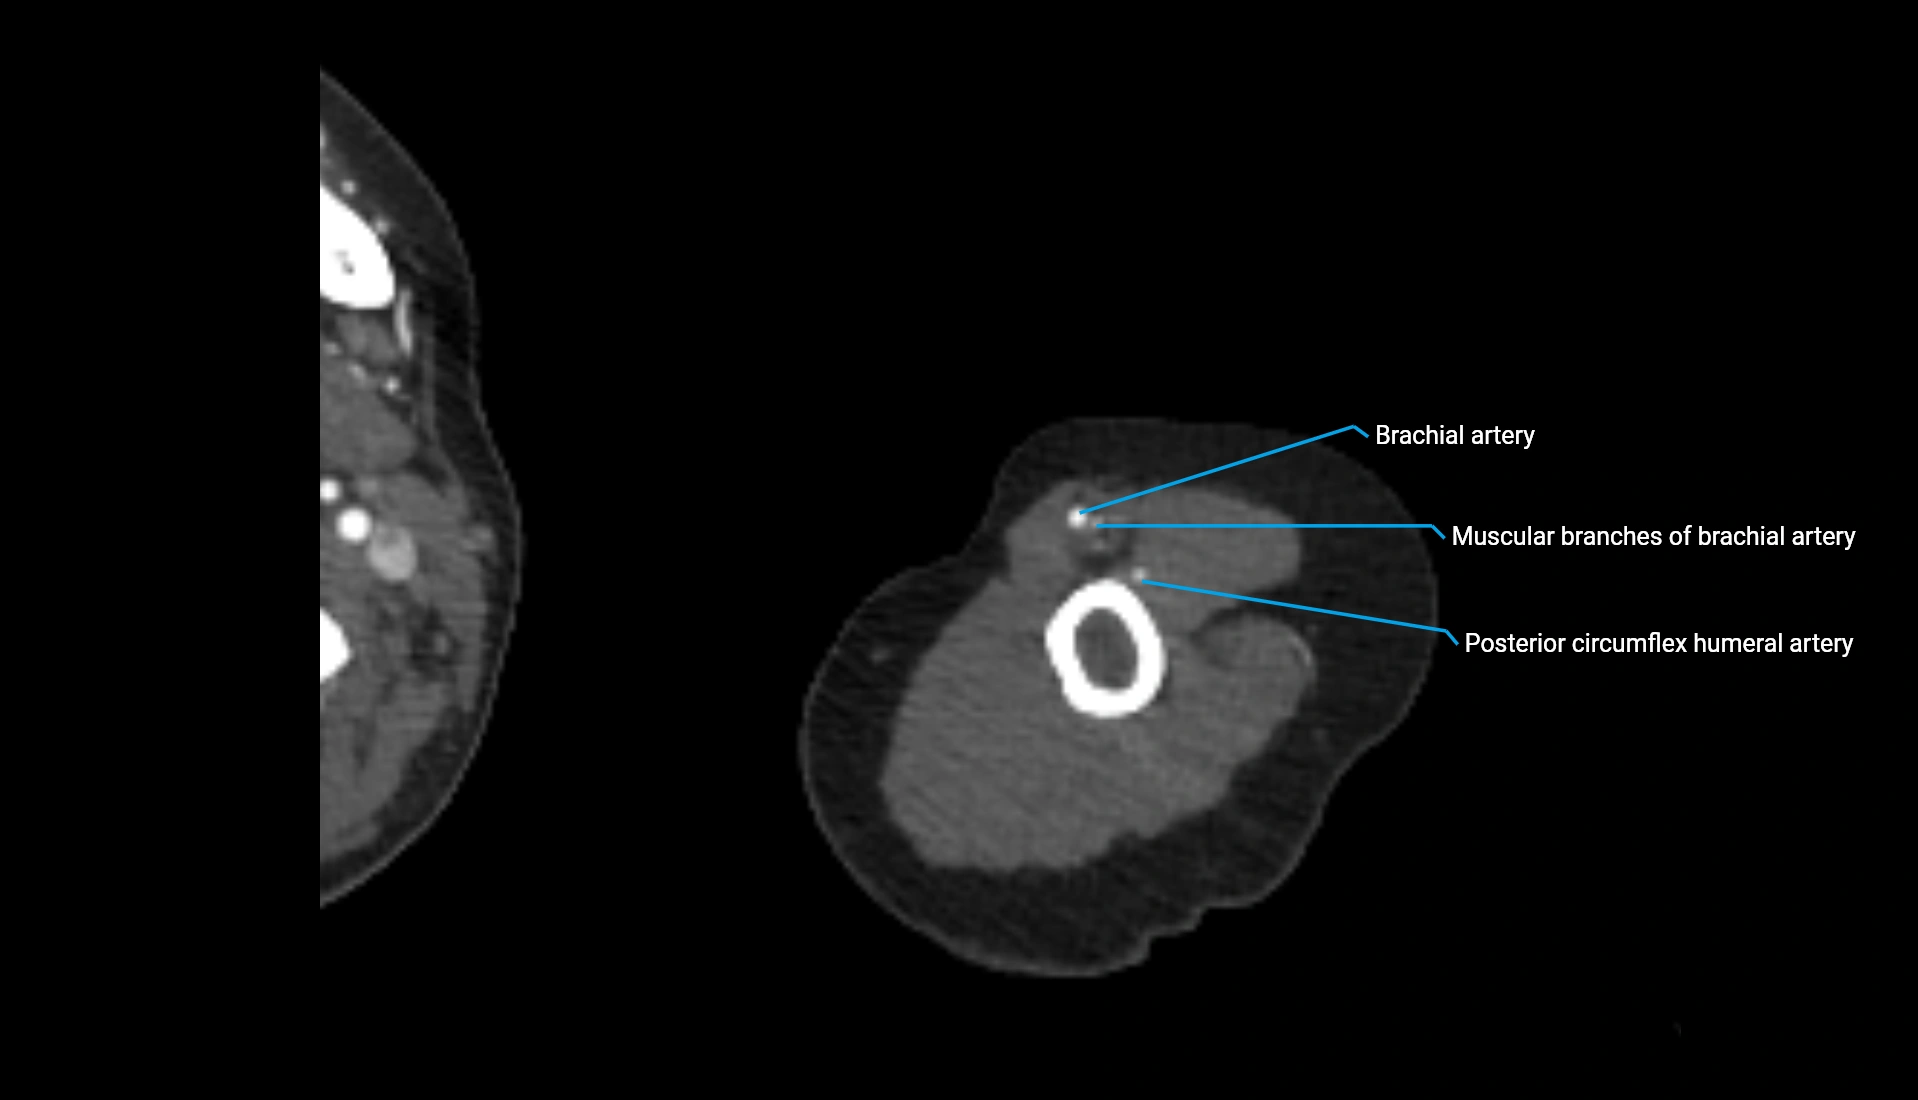

CT Appearance

Non-Contrast CT:

• Cortex: High-density, sharply defined

• Subchondral bone: Dense cancellous matrix

• Articular surface: Smooth concave contour articulating with the capitellum

• Excellent for evaluating bone integrity, alignment, and subtle fractures